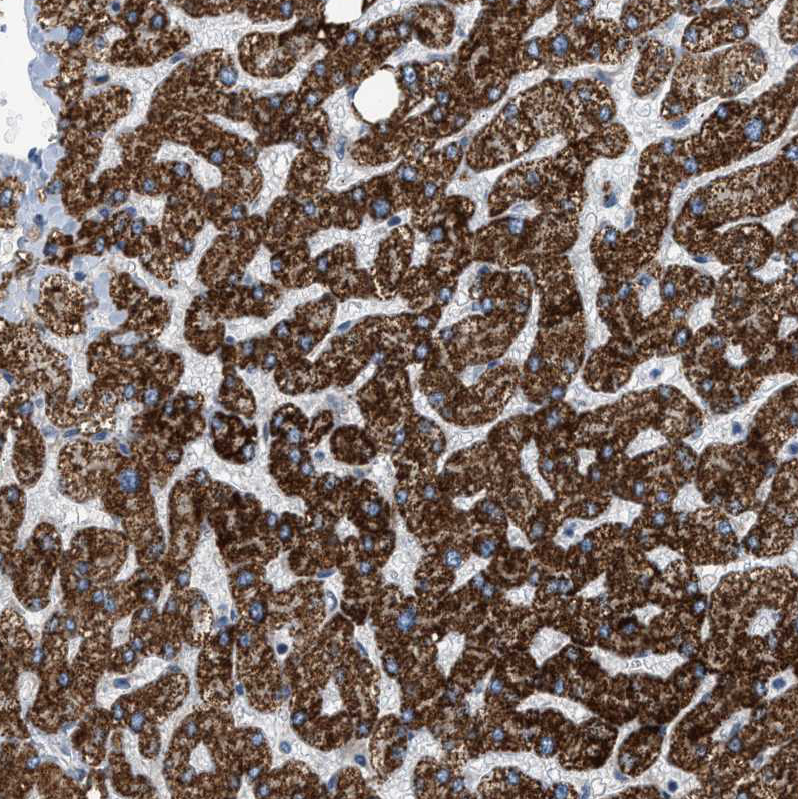

Immunohistochemistry analysis in human liver and bone marrow tissues using HPA018139 antibody. Corresponding GOT2 RNA-seq data are presented for the same tissues.